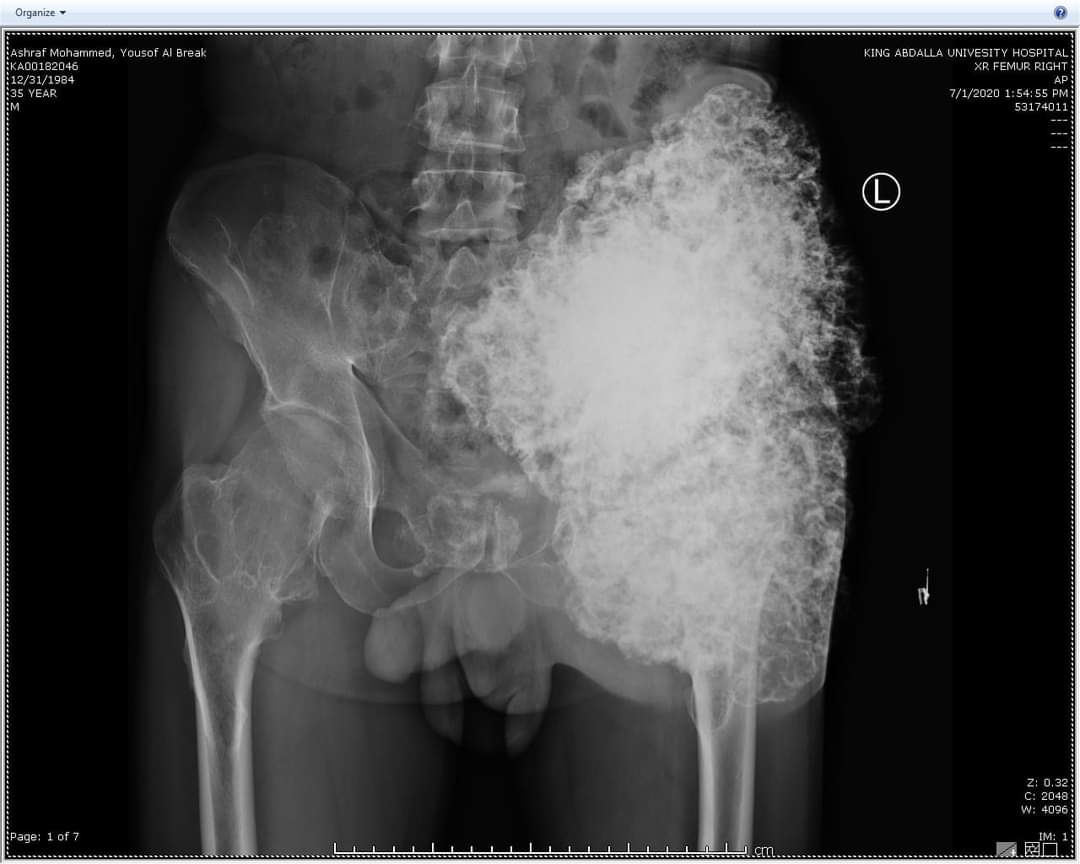

عملية نوعية لمريض ثلاثيني في مستشفى الملك المؤسس يعاني من ورم عظمي ضخم .. صور

تمكن قسم الجراحة الخاصة / شعبة العظام في مستشفى الملك المؤسس عبدالله الجامعي  من إجراء عملية نوعية لمريض ثلاثيني يعاني من ورم عظمي ضخم داخل تجويف الحوض ملاصق للأوعية الدموية والأوردة الرئيسية والأعصاب يزن قرابة (٥) كيلو غرامات يقع في منطقة ضيقة من منطقة الحوض الداخلية  بجانب تجويف البطن والأمعاء حيث ان هذه المنطقة يصعب الوصول اليها لمدى خطورتها .

وأجرى العملية فريق طبي بإشراف إستشاري جراحة أورام العظام  الدكتور زياد مهيدات وأستغرقت العملية الجراحية اربعة ساعات بعد أن تعذر إجراءها في مراكز طبية أخرى و تعتبر هذه العملية من العمليات الصعبة والمعقدة  حيث أظهرت الفحوصات والأشعة التي أجريت للمريض وجود ورم عظمي ضخم داخل تجويف الحوض من الجهة الداخلية الى خارج الجسم مع وجود إحتمالية تحوله الى ورم خبيث في أي لحظه حيث كان لزاماً ازالته مبيناً إن هذه العمليات يجريها بالعادة فريق جراحين متخصصين في مراكز متخصصة مثل هذا المركز الجامعي المميز والمجهز بأحدث الأجهزة والذي يشهد تقدماً كبيراً .